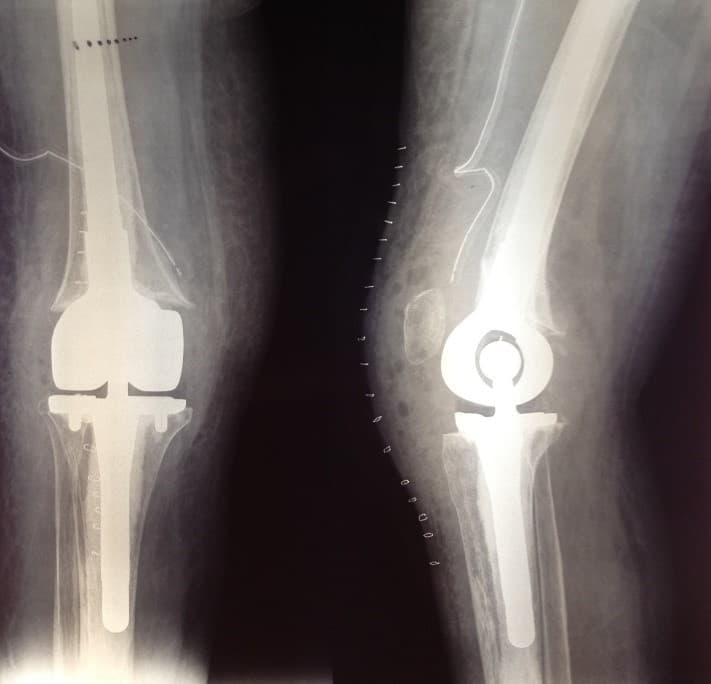

Үе дайрсан ясны анхдагч хавдар, ясны дутмагшлын үед хийгдэх мэс засалimg15Үе дайрсан ясны анхдагч хавдар, ясны дутмагшлын үед хийгдэх мэс засалimg16

Зураг 3. Мэс заслын дараах рентген зураг. Эгц урд, хажуугаас авсан байдал